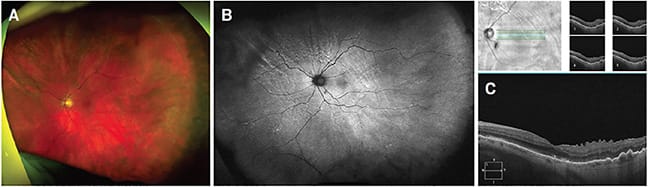

Over time, we saw consistent improvement symptomatically and on exam, so we canceled surgery and continued following him closely while slowly tapering him off of the medications. Once we deemed him stable enough for secondary IOL placement, an uneventful surgery took place to insert an anterior chamber intraocular lens around 9 months after presentation. He was last seen around 1 year after presentation, and everything looked fantastic: He had a VAsc of 20/70 (PH 20/40) and IOP 14 in his left eye. The retina was flat with peripheral pigmentary changes and rows of circumferential choroidal fold lines, and OCT showed a flat macula with mild ERM, ellipsoid zone changes, and improving choroidal folds (Figure 2).